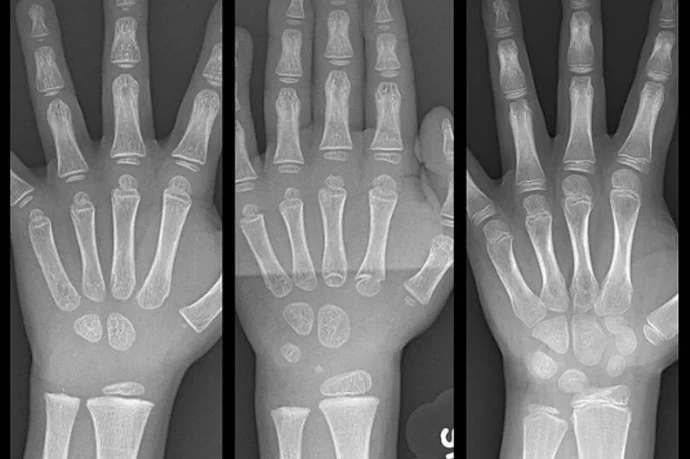

Przepieknie pokazuje to zdjecie rentgenowskie dloni ![]()